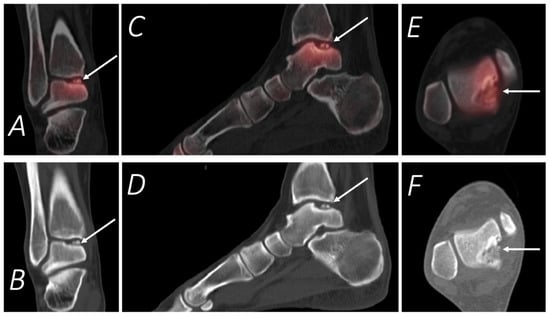

7. Knee Pain

- Mohan, H.K.; Gnanasegaran, G.; Vijayanathan, S.; Fogelman, I. SPECT/CT in imaging foot and ankle pathology-the demise of other coregistration techniques. Semin. Nucl. Med. 2011, 40, 41–51. [Google Scholar] [CrossRef]

- Leumann, A.; Valderrabano, V.; Plaass, C.; Rasch, H.; Studler, U.; Hintermann, B.; Pagenstert, G.I. A novel imaging method for osteochondral lesions of the talus—Comparison of SPECT/CT with MRI. Am. J. Sports Med. 2011, 39, 1095–1101. [Google Scholar]

- Wiewioski, M.; Rasch, H.; Jacob, A.L.; Valderrabano, V. Pain in osteochondral lesions. Foot Ankle Spec. 2011, 4, 92–99. [Google Scholar] [CrossRef]

- Breunung, N.; Fernando, R.; Gnanasegaran, G.; Vijayanathan, S.; Hosahalli, M.; Fogelman, I. Additional benefit of SPECT/CT in investigating heel pain. Clin. Nucl. Med. 2008, 33, 705–706. [Google Scholar] [CrossRef]

- Langroudi, B.; Gnanasegaran, G. SPECT-CT in the assessment of bony foot pathology. J. Nucl. Med. 2007, 48, 122–124. [Google Scholar]